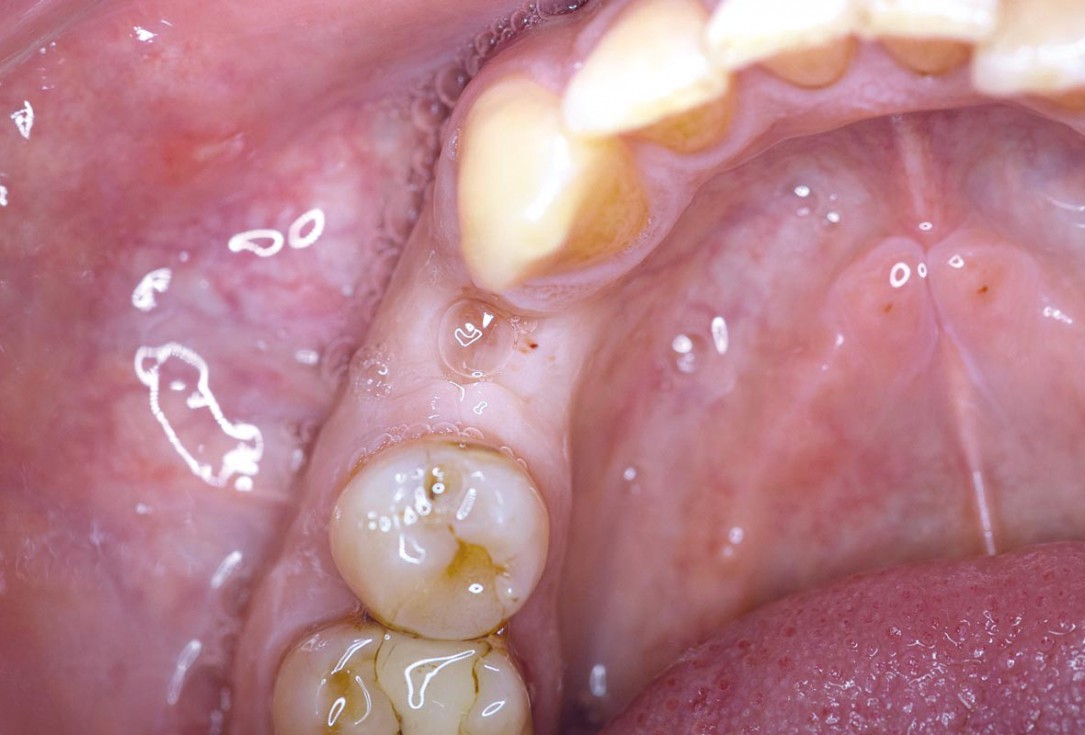

Posterior socket preservation using maxgraft® and permamem® - Dr. C. Landsberg

Tooth 16 furcation involvement with gingival marginal recession and large Class 5 filling